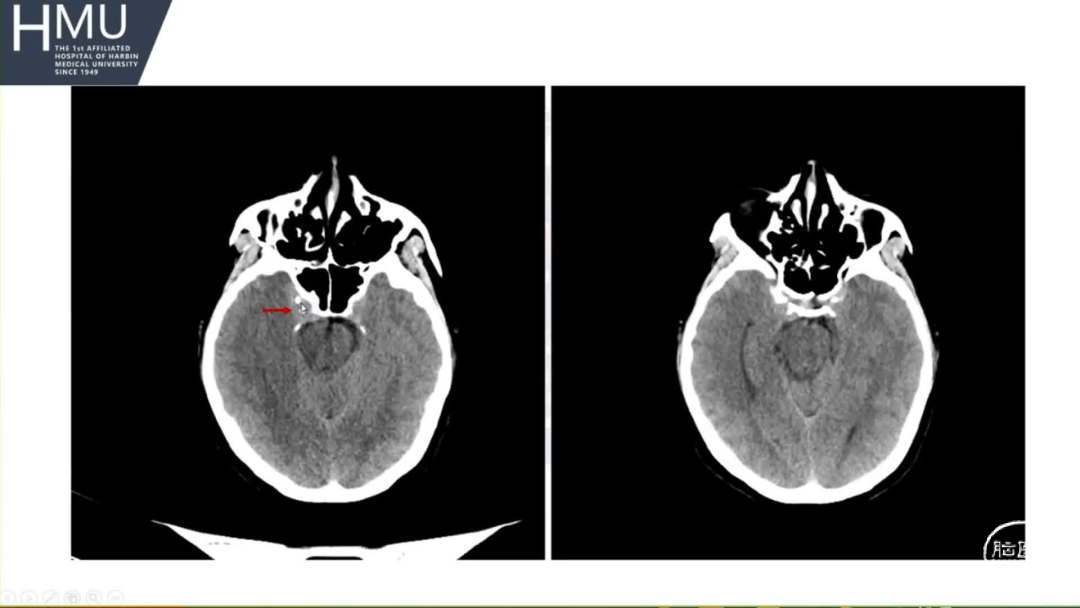

23日06:00

患者答非所问,查体不配合

急行头部CT

23日14:00患者刺痛不睁眼,不发声,

右上肢刺痛定位,左侧瞳孔光反射消失。

16:00急诊行钻孔引流术